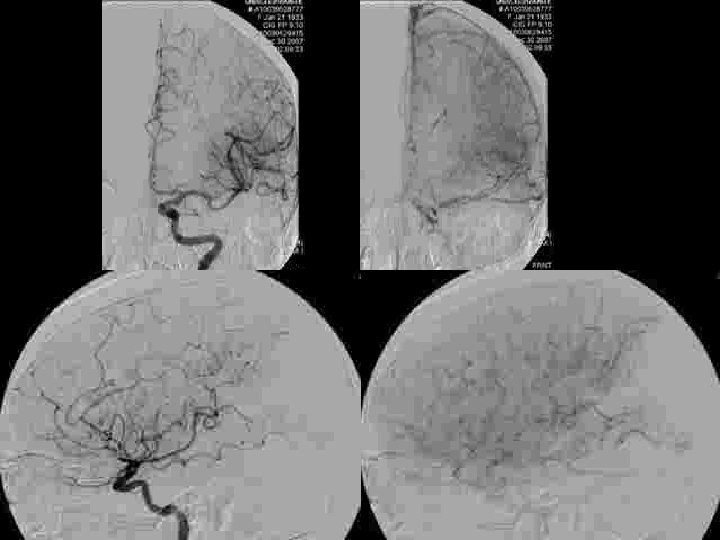

Sélection des patients • Être efficace : y a t’il du parenchyme a sauver ? – Diffusion : nécrose définitive! discutable: • diminution des zones d’anomalies de diffusion après thrombolyse IA • Hétérogénéité des niveaux de baisse d’ADC à l’intérieur de la zone anormale • diminution progressive de l’ADC de la périphérie vers le centre: notion de seuil? – < 50 % : évolution vers la nécrose certaine – >70 -80% : récupérable si recanalisation – Importance de l’évaluation de l’ischémie: • collatéralité en angiographie • perfusion en IRM ou en scanner

Sélection des patients imagerie • Efficace – – Est ce un AVC? Ischémique ou hémorragique? Mismatch? Occlusion persistante? • Rapide < 15 minutes Time is brain!! – MRI: Diffusion+3 d TOF MRA+ Perfusion. MR – CT scanner+angio CT+ perfusion CT

Sélection des patients • Ne pas être dangereux: identifier les patients à haut risque d’hémorragie – Localisation profonde – Délai – Baisse de l’ADC: risques si ADC< 33% – Hypoperfusion sévère : CBF< 33%

INDICATIONS • Thrombolyse à la carte ! Ou plutôt indication personnalisée: – Clinique – Diffusion – Perfusion – Angio-RM

Quelle technique pour quels patients? • IV: NINDS • tous type d’AVC (résultats moins bons pour les artères principales) • < 3 h • IA : PROACT II • NIHSS > 10 • < 6 h • Mismatch ? • Risque hémorragique?

Quelle(s) technique(s) pour quels patients? • • • NIHSS < 10 < 3 h IRM/CT ? r. Tpa IV +Abciximab? + Ultrasons? • • • NIHSS > 10 < 3 h IRM r. Tpa IA +Abciximab? r. Tpa IV? • NIHSS > 10 • > 3 h • IRM • Mécanique ± r. Tpa IA • ±Abciximab?

Quelle(s) technique(s) pour quels patients? Attitude nancéenne 2007 • IV – < 3 heures – « mismatch » ? – M 1 distal et au delà • IA – > 3 heures : toutes localisations – < 3 heures : TB, ACI, M 1 proximal – Mismatch diff/perf